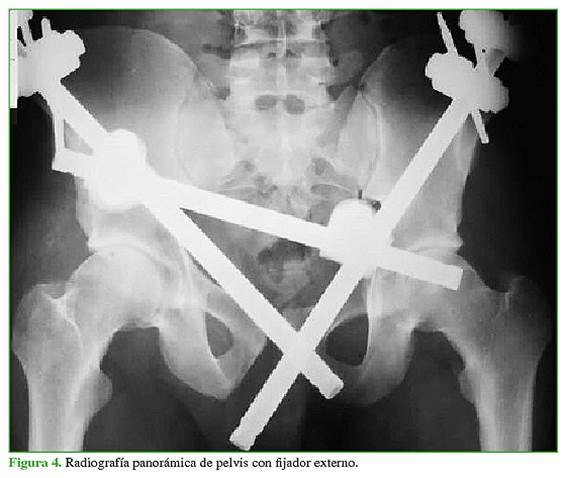

Las fracturas se clasificaron, según la clasificación de Young y Burgess, en las radiografías panorámica (Figura 1), de entrada (Figura 2) y de salida de pelvis (Figura 3), y tomografía computadorizada.

Se analizaron 23 pacientes con diagnóstico de fractura de pelvis APCII (16 hombres y 7 mujeres). La mediana de la edad era de 32 años (rango 15-70). El seguimiento promedio fue 3.2 años (mín. 2, máx. 6). En nueve pacientes (39,13%), se documentaron lesiones asociadas. El tratamiento en la urgencia fue con cincha pélvica en 19 pacientes (82,61%), con fijador externo en dos (8,69%) (Figura 4) y dos (8,69%) fueron estabilizados hemodinámicamente mediante packing pélvico. La mediana de espera hasta la cirugía definitiva fue de 10 días (rango 1-60).